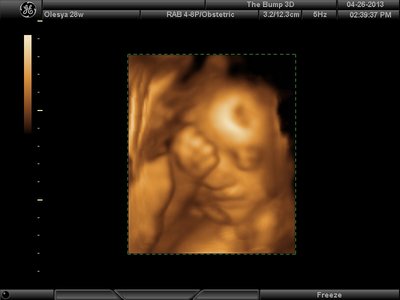

Еще одна, качество ужасное..

| Вложения: |

image.jpg [ 60.32 КБ | Просмотров: 1437 ]